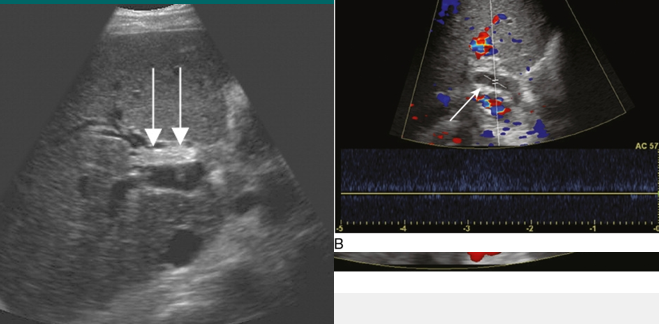

cavernous transformation of PV